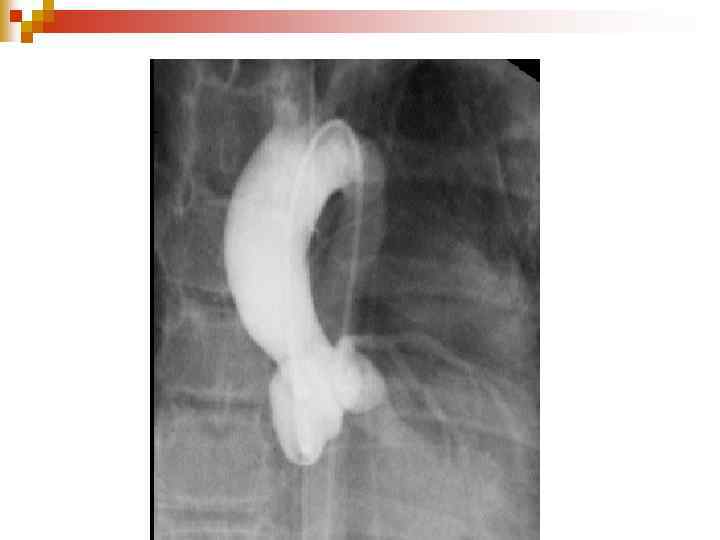

Відкрита артеріальна протока

n Серце злегка збільшене, основа легеневої артерії і дуги аорти випукла. Збагачення легеневого судинного малюнку